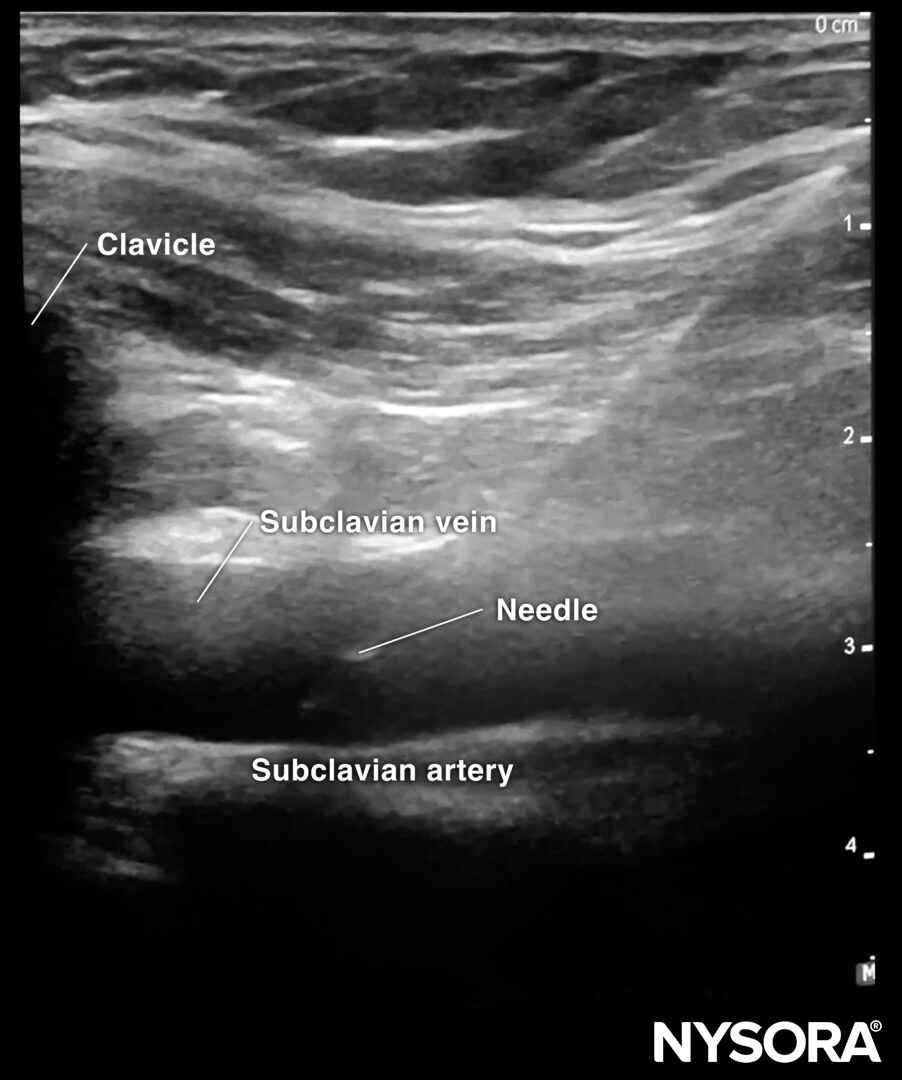

First, the transducer is placed in a longitudinal orientation to the clavicle next to the deltopectoral groove. Identify the subclavian artery and vein, and position the vein in the middle of the screen. Rotate the transducer until the vein is seen in line. Now, you should also see the bony shadow of the clavicle.

Sonoanatomy for subclavian vein cannulation.

The needle is inserted in-plane in a cranial direction.

In-plane needle insertion in the subclavian vein.